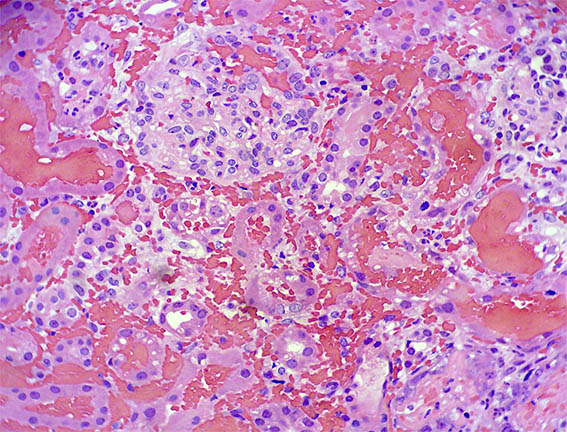

Figure 2. Masson's trichrome stain, X100.

Figure 3. H&E, X200.